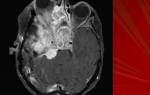

- Онкогенные опухоли. Герпетическая инфекция может приводить к онкологическим заболеваниям любой локализации. Злокачественные опухоли поражают женские репродуктивные органы, головной мозг, лейкемии.

- энцефалит;

Вирус герпеса человека 6 типа – это бета герпетический вирус, вызывающий внезапные экзантемы у детей, мононуклеоподобный синдром, синдромы хронической усталости и энцефаломиелиты. У пациентов со СПИДом герпес 6 типа стимулирует развитие оральных цервикальных карцином.

Также герпес 6 типа может провоцировать развитие синдрома Шегрена, лимфогранулематозов, злокачественных клеточных лимфом, саркоидоза, фебрильных судорог у детей.

Зарегистрированы случаи развития тяжелых герпесных гепатитов, связанных с вирусом герпеса 6 типа. При этом, течение такого гепатита носит преимущественно фульминантный (внезапный и быстро развивающийся) характер и часто заканчивается летальным исходом.

- ткани головного мозга;